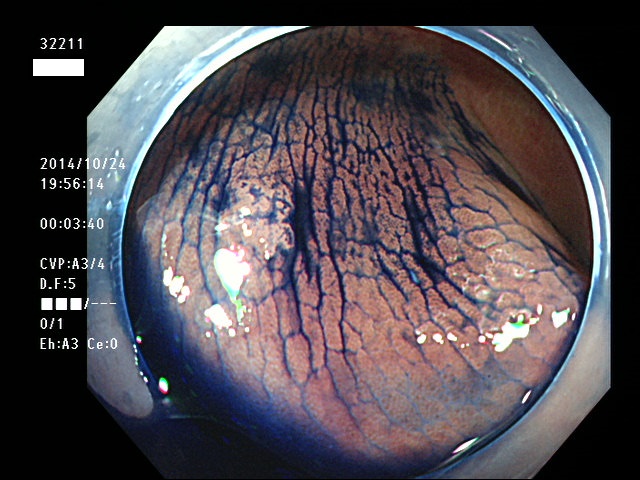

上記100名より抽出した平坦・陥凹型腺腫(=癌化の危険が高いが見落としやすい病変)の内視鏡写真